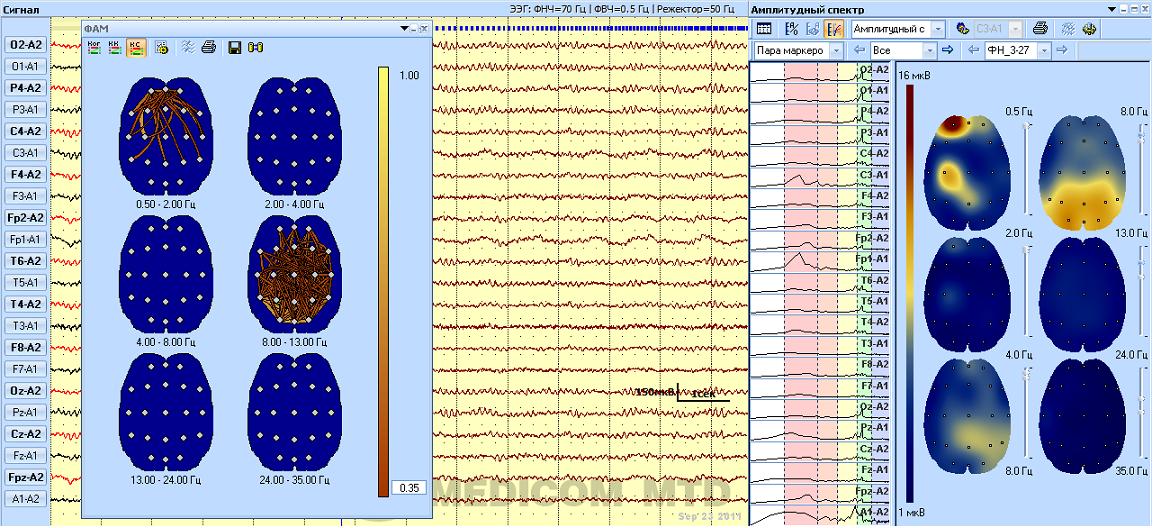

Известно, что при ”здоровом”, т.е. нормальном биологическом старении меняется функционированиe мозга. Когда констатируются соматические заболевания, речь идёт о преждевременном старении или отдельных его признаках, а наличие неврологических заболеваний ведёт к патологическому старению или даже слабоумию. Некоторые изменения при старении мозга являются общими, свидетельствующими о небольшой атрофии мозговой ткани (Елхон Голберг, 2005). Кровоток мозга, поступление кислорода и питательных веществ становятся менее обильными и, вследствие этого, может снизиться функциональная активность коры головного мозга в целом или отдельных ее зон. Так, Д.Х. Джексоном было показано, что прежде всего изменяется функционирование более молодых кортикальных зон - ассоциативных и гетеромодальных, особенно нарушается переднелобная кора, отвечающая за комплексное планирование и организацию сложных форм поведения. Учитывая, что электрическая активность мозга отражает характер и особенности корко- подкоркового функционирования мозга, она может служить одним из ранних маркеров старения, поэтому важно знать состояние возрастных нейрофизиологических особенностейсвоего мозга (ЭЭГ количественная и функциональная) .

Регистрация электрической активности мозга в состоянии покоя

Э лектрическая активность мозга при решении логических задач (возраст 65 лет)

ЭЭГ изменения в функционирования мозга в большинстве случаев остаются скрытыми и неосознаваемыми , долго не проявляются какими - либо психическими отклонениями или поведенческими особенностями. Они выявляются неожиданно, довольно резко в те периоды жизни, когда к организму предъявляются повышенные требования. Это могут быть стрессовые состояния, интеллектуальные или эмоциональные перегрузки , соматические заболевания . Так же скрытно, без жалоб на ухудшение состояния здоровья протекают и начальные стадии ускоренного патологического старения мозга. В первую очередь это относится к болезни Альцгеймера и старческой деменции Альцгеймерского типа. Однако изменения ЭЭГ достаточно четко выявляют как самые ранние признаки нарушений функционирования мозга , которые опережают проявление этих изминений в поведенческих реакциях. По современным представлениям общее и локальное снижение мощности ритмов в динамике может свидетельствовать о снижении функциональной активности нейронов коры мозга, которая постепенно ведет к атрофии (дегенерации) мозгового вещества, что в свою очередь постепенно приводит к снижению умственных способностей и неуклонно нарастающей деме нции.